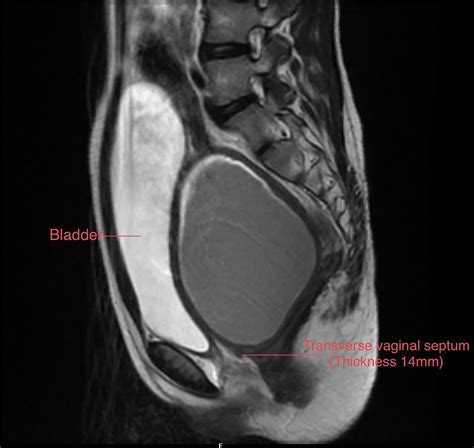

MRI (Magnetic Resonance Imaging) Provides a high-resolution view of the vaginal anatomy and the thickness of the septum.

💡 Note: MRI is generally preferred over ultrasound for surgical planning because it provides a precise measurement of the septum’s thickness and distance from the introitus, which is vital for the surgeon.

The primary treatment for a Transverse Vaginal Septum is surgical correction. The goal is to remove the obstructive tissue and restore the patency of the vaginal canal. The specific surgical approach depends on the thickness of the septum and the patient’s overall anatomy.

• Z-plasty or Flap Techniques: When the septum is thick or long, a simple excision may lead to vaginal stenosis (narrowing/scarring). Surgeons use specialized tissue-rearrangement techniques to prevent post-operative narrowing.